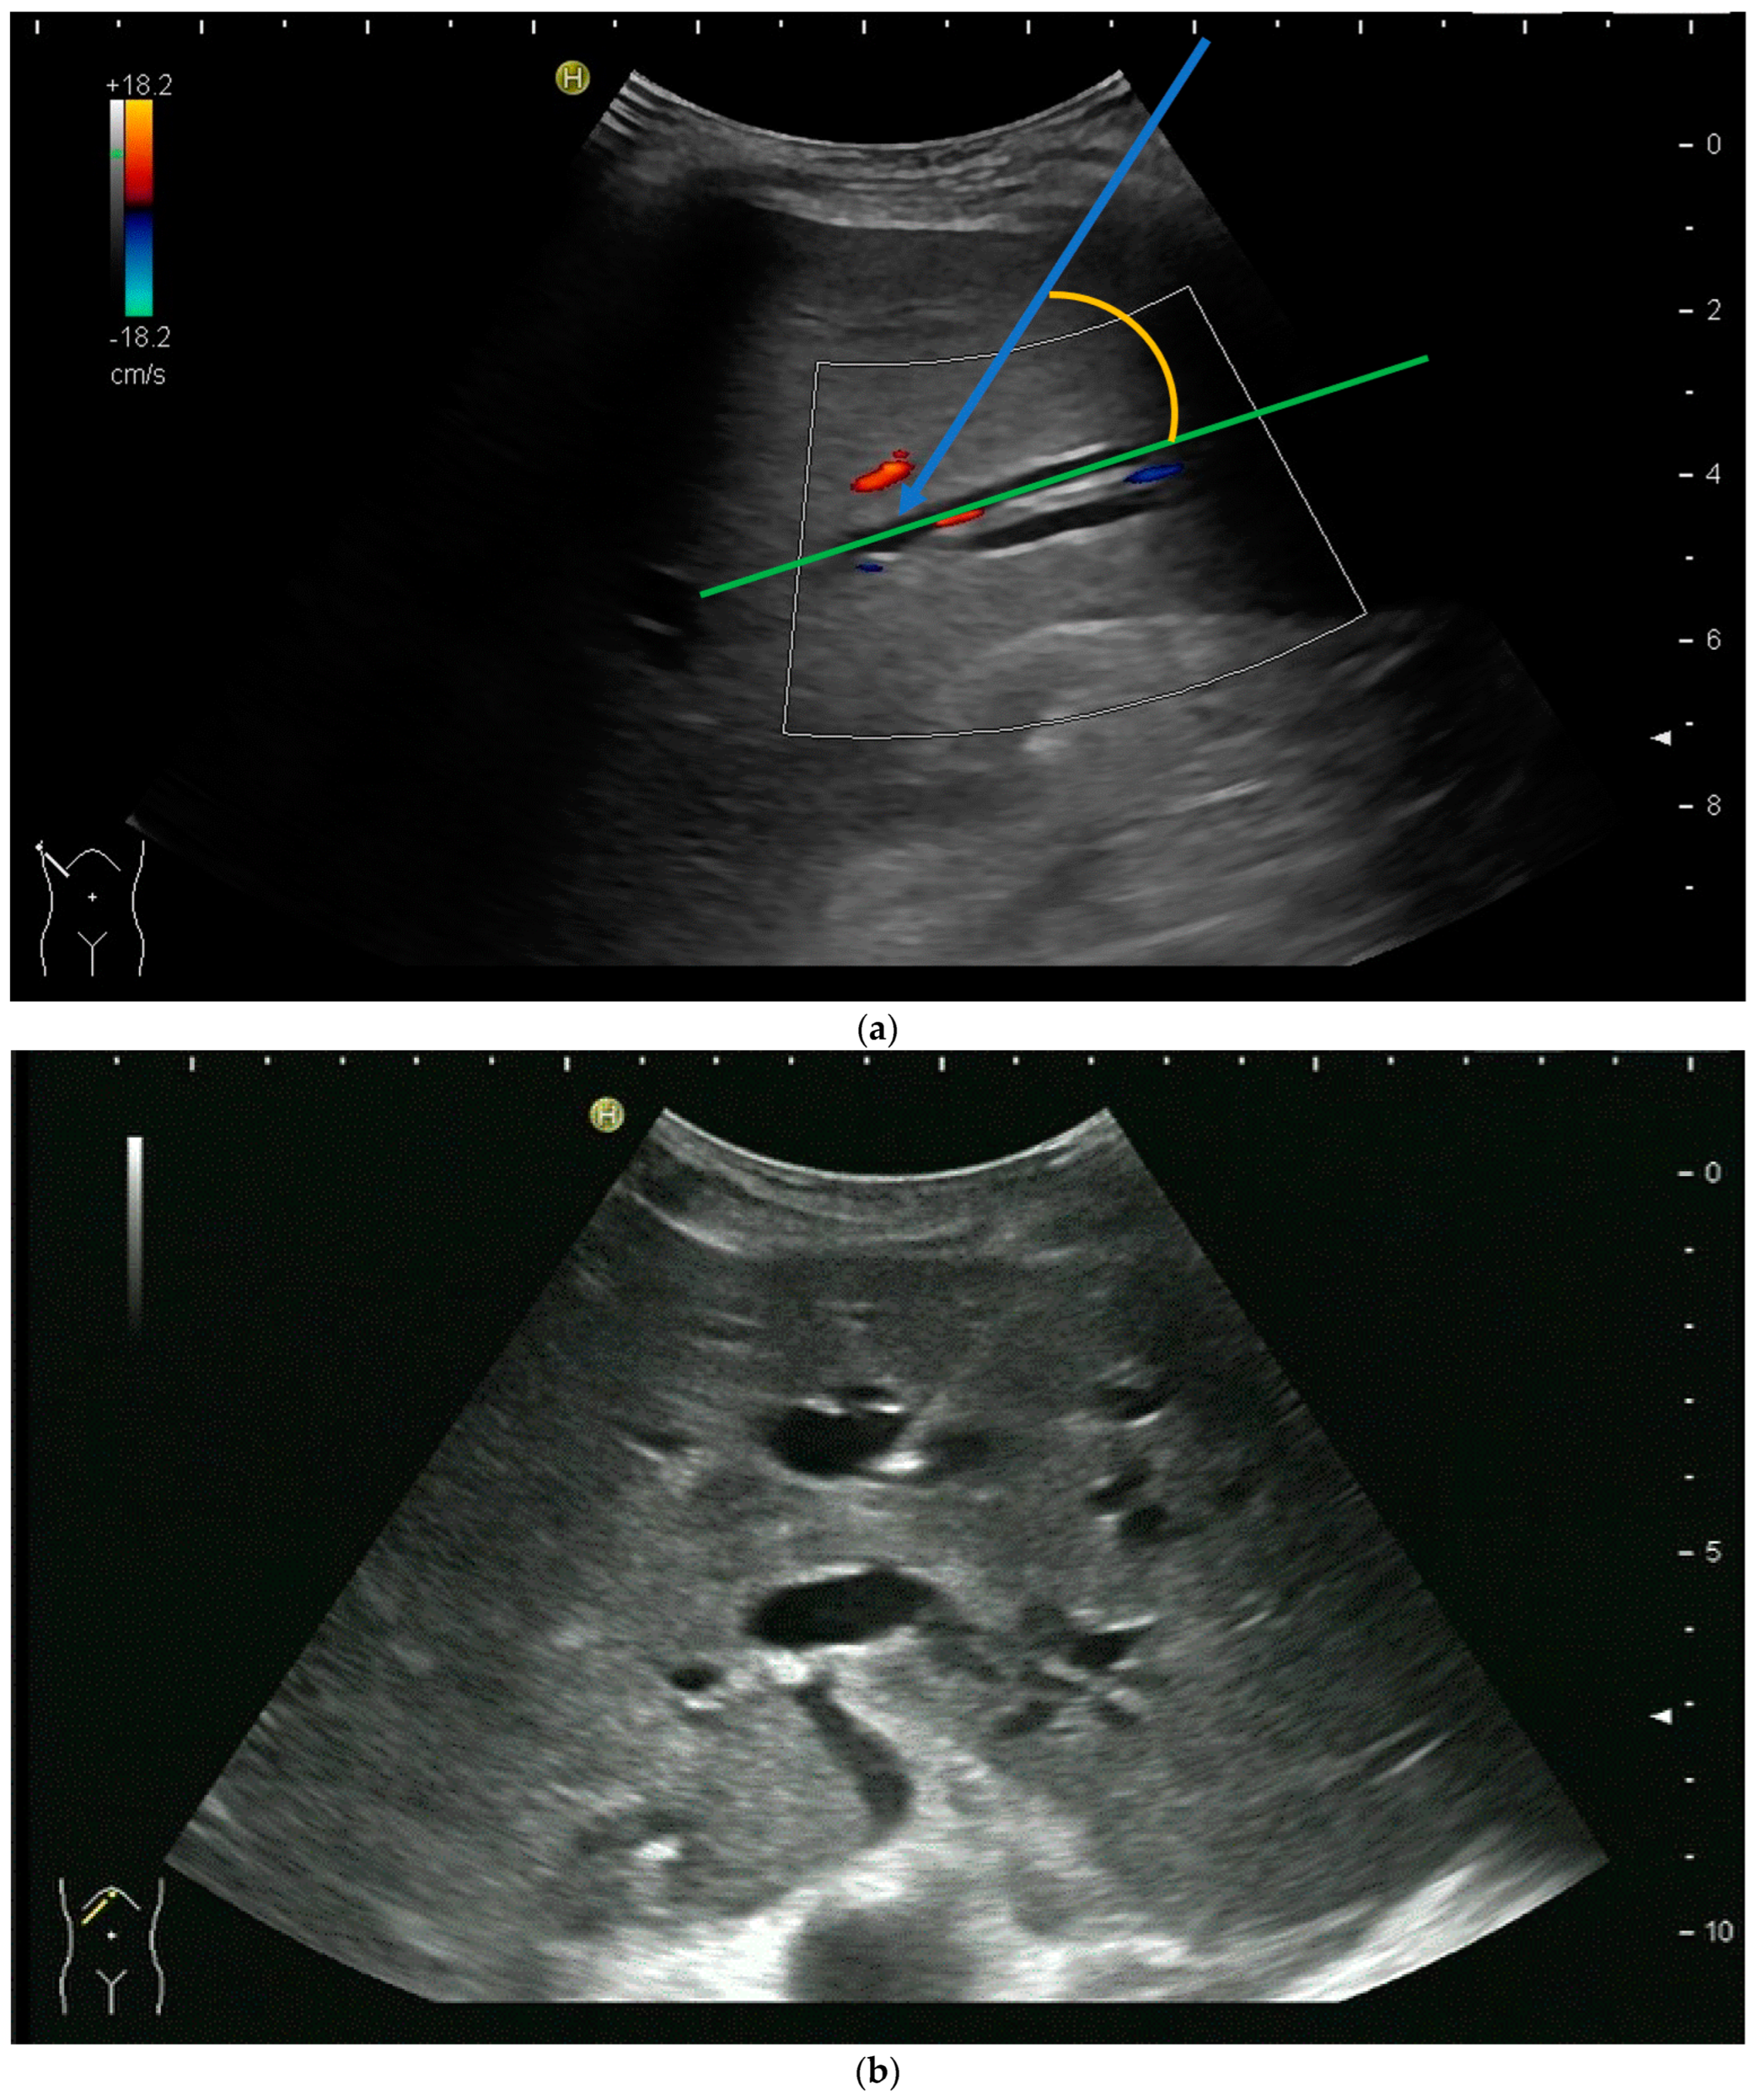

PTBD is commonly performed in the so-called “in plane technique” (Figure 1a,b).

(a) Puncture in plane. The needle is inserted at the centre of the small side of the transducer; (b) Needle tip (yellow arrow), body (white arrows), and target (bile duct) are depicted in one plane. The needle tip is kept in plane by very small movements of the transducer.

However, the “free hand” technique allows for every puncture angle and is, therefore, preferred by us. The use of colour Doppler will enable the doctor to avoid blood vessels and identify smaller bile ducts (Figure 3a,b).

(a) Hypoechoic tubular structures in Segment V are visualised in an intercostal view; (b) Colour Doppler helps to differentiate between bile ducts and blood vessels.

In cases of extrahepatic obstruction, mostly the right liver lobe will be addressed. It is common practice to head for the peripheral branches in Segment V (cf. Figure 3a,b), as from there to the common bile duct, the biliary branches form a harmonic arch, and the forward movement of the guide wire seems unpretentious [3]. However, US guidance allows the puncture of any biliary duct of the right or left liver lobe that can be depicted well (Figure 4a–c).

(a) A pointed angle between the needle trajectory and a bile duct of Segment V/VI is given; (b) Puncture of a dilated bile duct in Segment IV at a suitable angle. A guide wire with a bended tip should be used to facilitate the correct advancement; (c) A guide wire is placed in a dilated intrahepatic bile duct in Segment III.